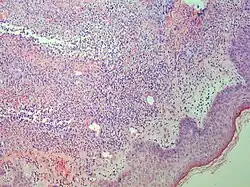

| Pigmented purpuric dermatosis |

|